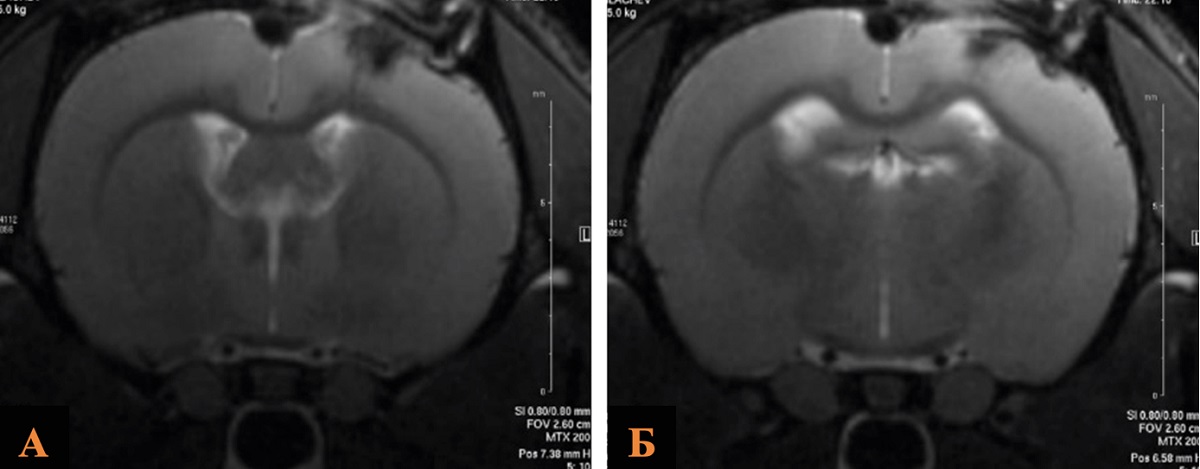

Исследование объема повреждения головного мозга проводили по данным морфометрического анализа МР-томографических изображений в группах ложнооперированных животных (n = 10), контрольных (n =10) и группе ОЧМТ+Литий 180 мин/21 мг (n = 10).

Анализ полученных данных выявил статистически незначимые различия в исследуемых группах: средний объем церебральных повреждений в группе ОЧМТ+Литий 180 мин/21 мг был меньше, чем в контрольной группе и составил 31,5 и 35,0 mm3 соответственно (рис. 4, табл. 4).

Рис. 4. МРТ зоны ушиба головного мозга крысы после введения хлорида лития в дозе 21 мг/кг через 180 мин в сравнении с контрольной группой

Примечание: А – группа Контроль; Б – группа ОЧМТ+Литий 180 мин/21 мг. Изображение авторов, получено в ходе оригинального исследования.

Таблица 4

Объем повреждения головного мозга крыс в группе ОЧМТ+Литий 180 мин/21 мг и группах сравнения по данным МРТ-изображений на 14-е сутки наблюдения

Группа | Объем повреждения головного мозга мм 3 | p, значимость относительно ложнооперированных животных | p, значимость относительно контрольных животных |

Ложнооперированные животные (n = 10) | 12,0 [8,0–14,5] | – | – |

Контроль (n = 10) | 35 [30–36] | 0,0001 | – |

ОЧМТ+Литий 180 мин/21 мг (n = 10) | 31,5 [25–33,5] | 0,001 | 0,09 |

Примечание: составлено авторами.

На основании полученных данных можно утверждать, что применение методики терапии хлоридом лития (4,2 % раствор в/в в дозе 21 мг/кг) через 180 мин после моделирования ОЧМТ у крыс линии Вистар снижает объем повреждения головного мозга крыс на 10 %.